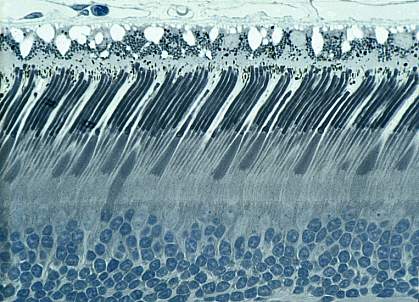

Cells in the eye called rods and cones are the ones primarily responsible for detecting light. They send signals to the brain through retinal ganglion cells (RGCs) so the brain can form our perception of images.

About 2% of RGCs—called intrinsically photosensitive RGCs, or ipRGCs—make a protein called melanopsin that allows them to sense light on their own and send information about light intensity to the brain. Previous research has shown that mice genetically engineered to lack melanopsin have reduced non-image-forming functions like pupil constriction. But because the mice don’t completely lose these functions, rods and cones must also be sending non-image-forming signals to the brain. A research team led by Dr. Samer Hattar at Johns Hopkins University set out to discover which RGCs are responsible for relaying these signals from the rods and cones. Their work was supported by NIH’s National Institute of General Medical Sciences (NIGMS), National Eye Institute (NEI) and other sources.